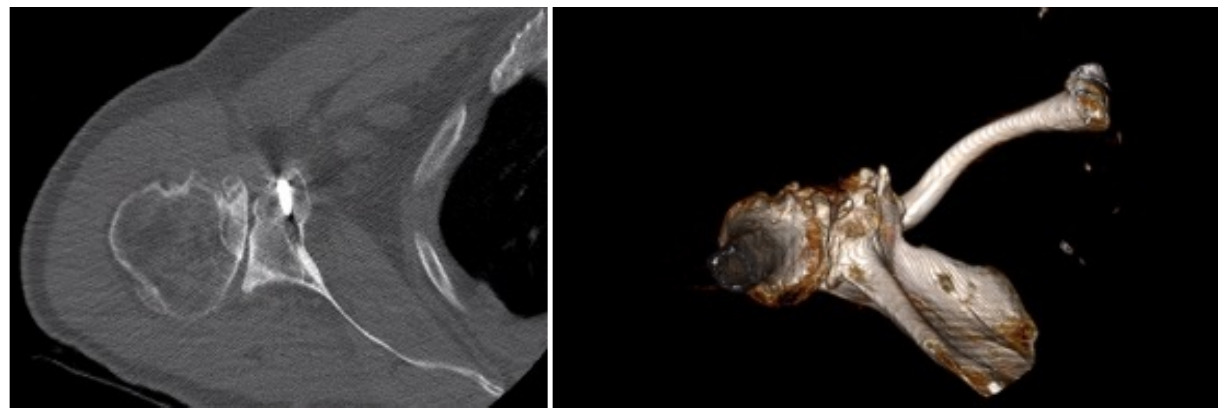

Case one is a 58-year-old male who is an avid golfer with long standing right shoulder pain. Surgical history includes previous Bristow procedure 30 years prior. Current Subjective Shoulder Value (SSV) is 30% and pain is 8/10 at baseline. Active range of motion was 110° of forward flexion, -10° of external rotation and interna rotation to the lateral buttock. Radiographs (Figure 1) and computed topography (CT) scan (Figure 2) show retained implants with loss of joint space, glenoid retroversion, and significant posterior humeral head subluxation. The patient had failed conservative management and was indicated for arthroplasty. Due to significant posterior bone loss and retroversion, an augmented anatomic component was selected for this patient. Radiographs at one year show a well seated glenoid component with restoration of the joint line and a centered humeral head (Figure 3). At five years, SSV had improved to 95% with excellent clinical motion (Figure 4).